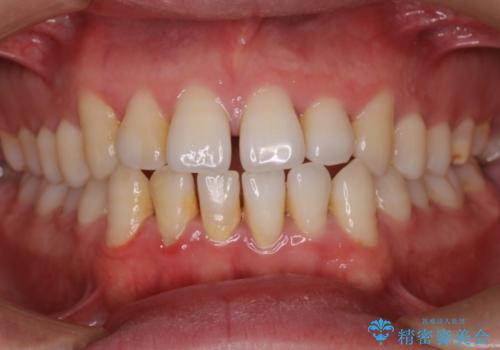

前歯で噛めない:オープンバイト(開咬)を非抜歯インビザラインで治療

- 上下の歯が噛んでいないことを気にしてご相談にいらした方です。

オープンバイトの方への治療は、通常抜歯を行いワイヤーによる矯正治療を行うことが多いですが、今回はインビザラインの特性を生かし、非抜歯にて綺麗な歯並びを作ることが出来ました。

舌癖がある方は、歯を内側から押し出す力が日常的に働くため、矯正治療後も歯と歯の隙間が開いてしまうなどの後戻りのリスクが高いことが知られています。舌の正しいポジショニングやお口周りの筋肉のトレーニングを行うことで後戻りのリスクを減らすことが可能です。